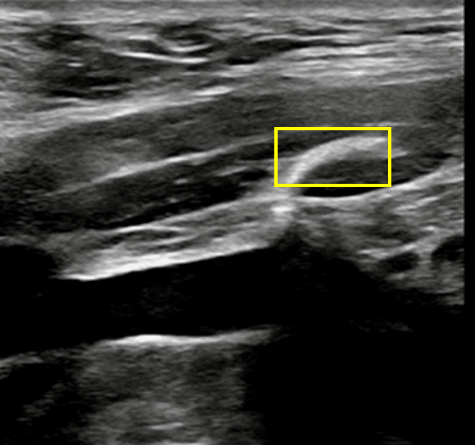

超声可见临时封堵盘贴合血管壁,胶原蛋白精准部署